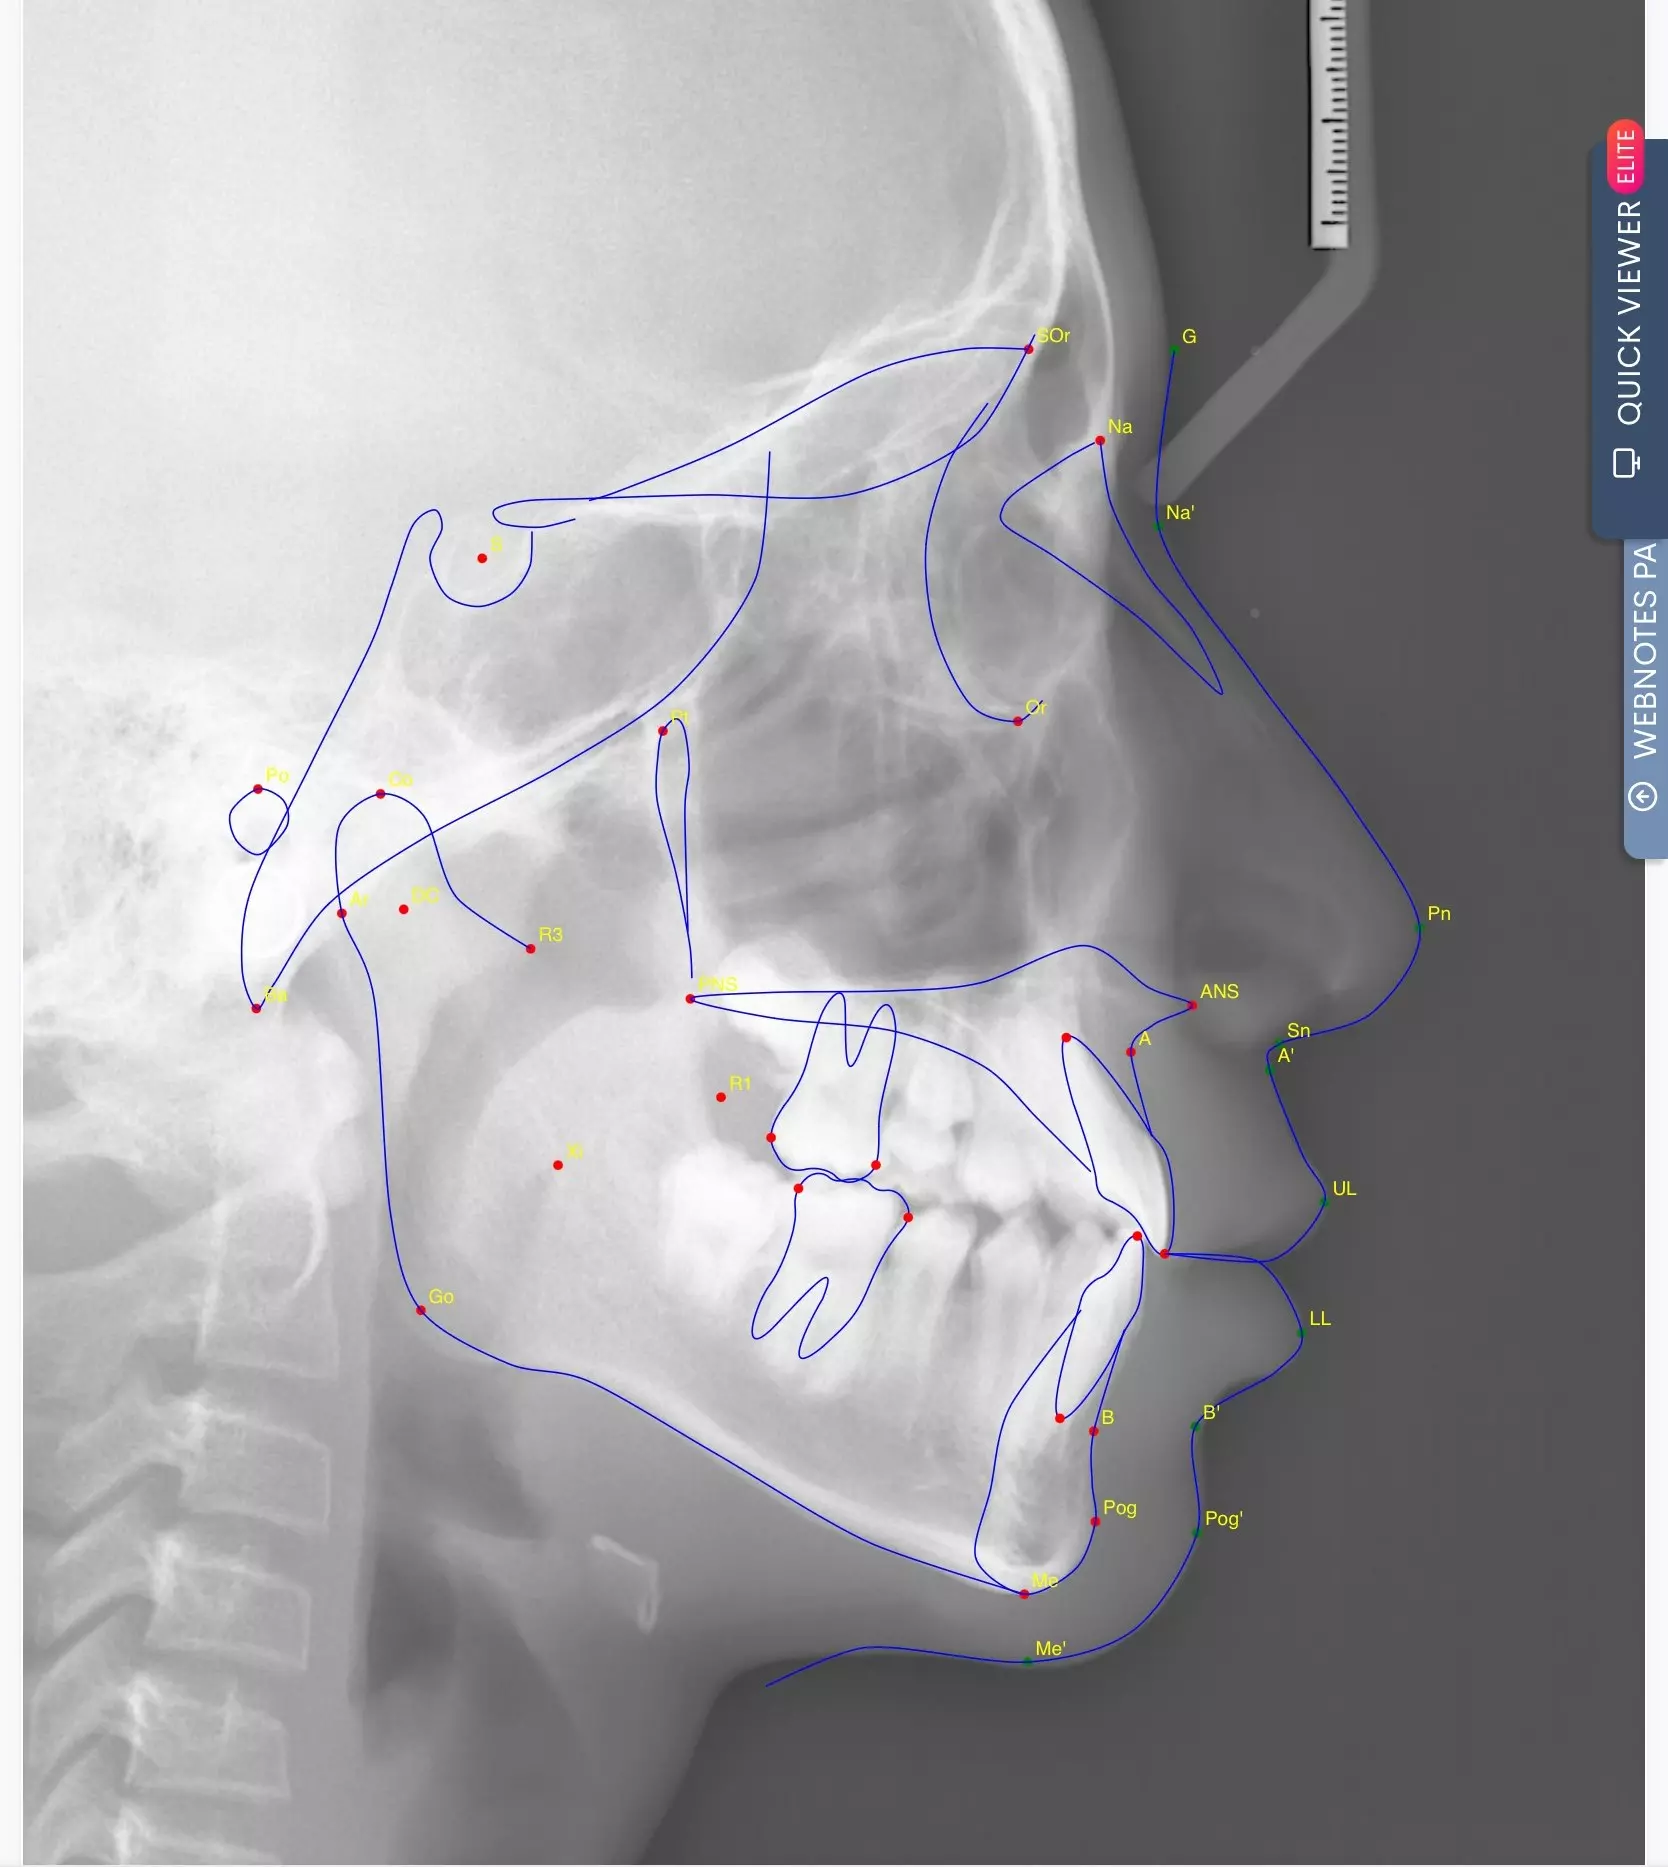

經過仔細檢查後,我們確認他屬於功能型第三類咬合異常 (Functional Class III)。這和大家熟知的「骨性戽斗」不同,他的狀況主要是因為牙齒排列影響了上顎的發育。這類型的咬合異常,如果沒有及早治療,可能會影響上顎的生長空間,進而讓整體顏面外觀及咬合狀態惡化。

因此,我們建議及早開始矯正,讓孩子的顎骨發育回到正常軌道,並減少未來可能面臨的複雜治療。

對於這類咬合異常,如果拖到青春期甚至成年,可能就需要更大規模的矯正,甚至外科手術才能改善。因此,我們會透過精細的檢查與評估,找出孩子最適合的治療時機與方式,讓治療事半功倍。